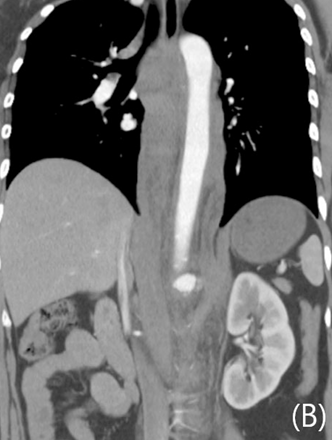

전산화단층촬영에서 자상으로 인해 대동맥에 거짓동맥류와 이와 관련한 광범위한 후복강 혈종이 보이고 있음 (Fig. 1A, B). 거짓동맥류가 생긴 위치는 복강동맥이 기시하는 높이의 뒤쪽 왼쪽인 5시 방향이었음. 이와 연관된 혈종은 후복강의 대동맥 주변과 횡격막 다리의 뒤쪽을 따라 연장되어 있었음. 그 외 다른 흉강이나 복강내 장기의 손상은 동반되지 않았음.

Fig 1A

Contrast-enhanced axial (A), coronal (B) CT scan demonstrates ruptured pseudoaneurysm (arrows) at posterior aspect of abdominal aorta causing redundant hemoretroperitoneum.

Fig 1B